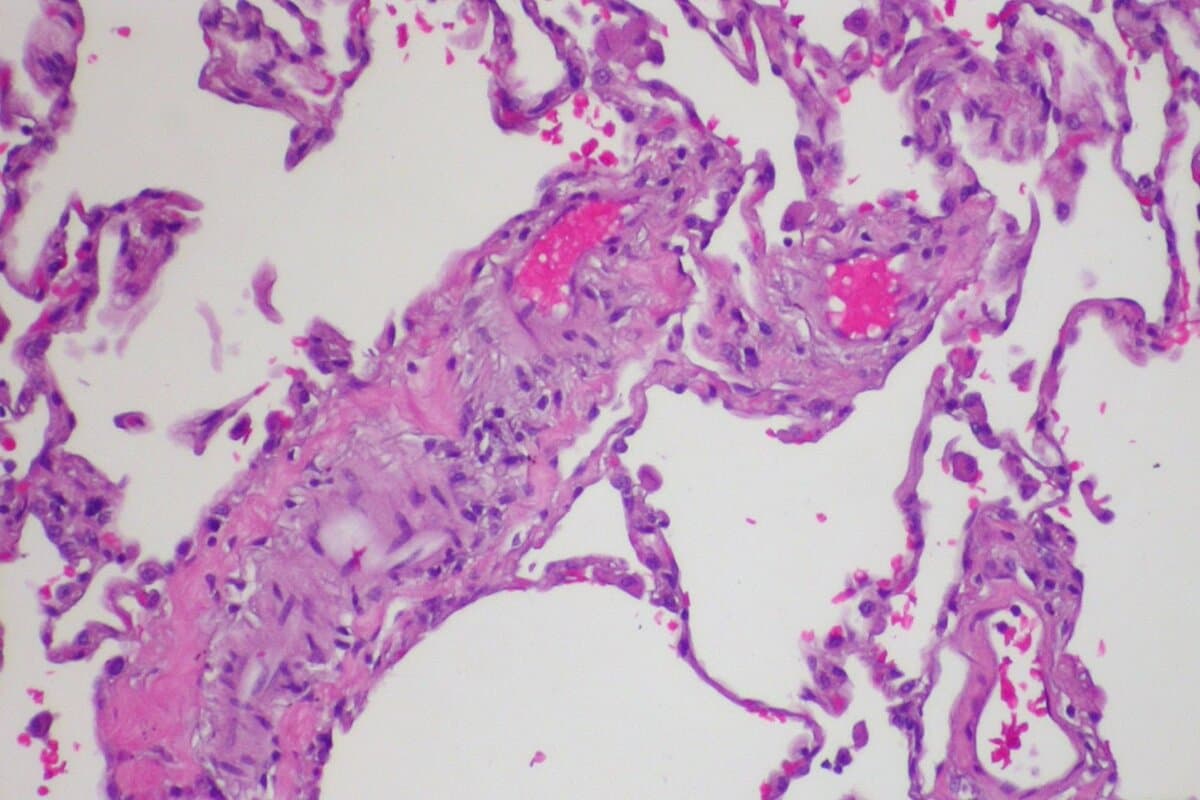

Gemäss der 2022 aktualisierten ESC/ERS-Leitlinie gehört die «PAH mit Merkmalen einer venösen/kapillären (PVOD/PCH) Beteiligung» nun zu 1.1 innerhalb der Gruppe 1 der klinischen PH-Klassifikation. Sie bildet nicht länger eine spezielle Subgruppe. Auch wenn Evidenz dafür besteht, dass PVOD und PCH verschiedene Formen derselben Erkrankung sind, werden sie im vorliegenden Beitrag unter dem Begriff PVOD zusammengefasst.

Fortschreitende Atemnot, Fatigue und Belastungsintoleranz sind typische Symptome, die sowohl bei PVOD als auch bei anderen PAH auftreten können. Jedoch weisen PVOD-Patienten tendenziell eine schwerere Symptomatik auf, die meist durch eine ausgeprägte Dyspnoe und Hypoxämie gekennzeichnet ist.

Im Lungenfunktionstest zeigt sich bei PVOD eine reduzierte Diffusionskapazität für Kohlenmonoxid bei erhaltenem Lungenvolumen. Hinsichtlich der pulmonalen Hämodynamik lassen sich keine bedeutenden Unterschiede zu anderen Formen des präkapillären Lungenhochdrucks feststellen.